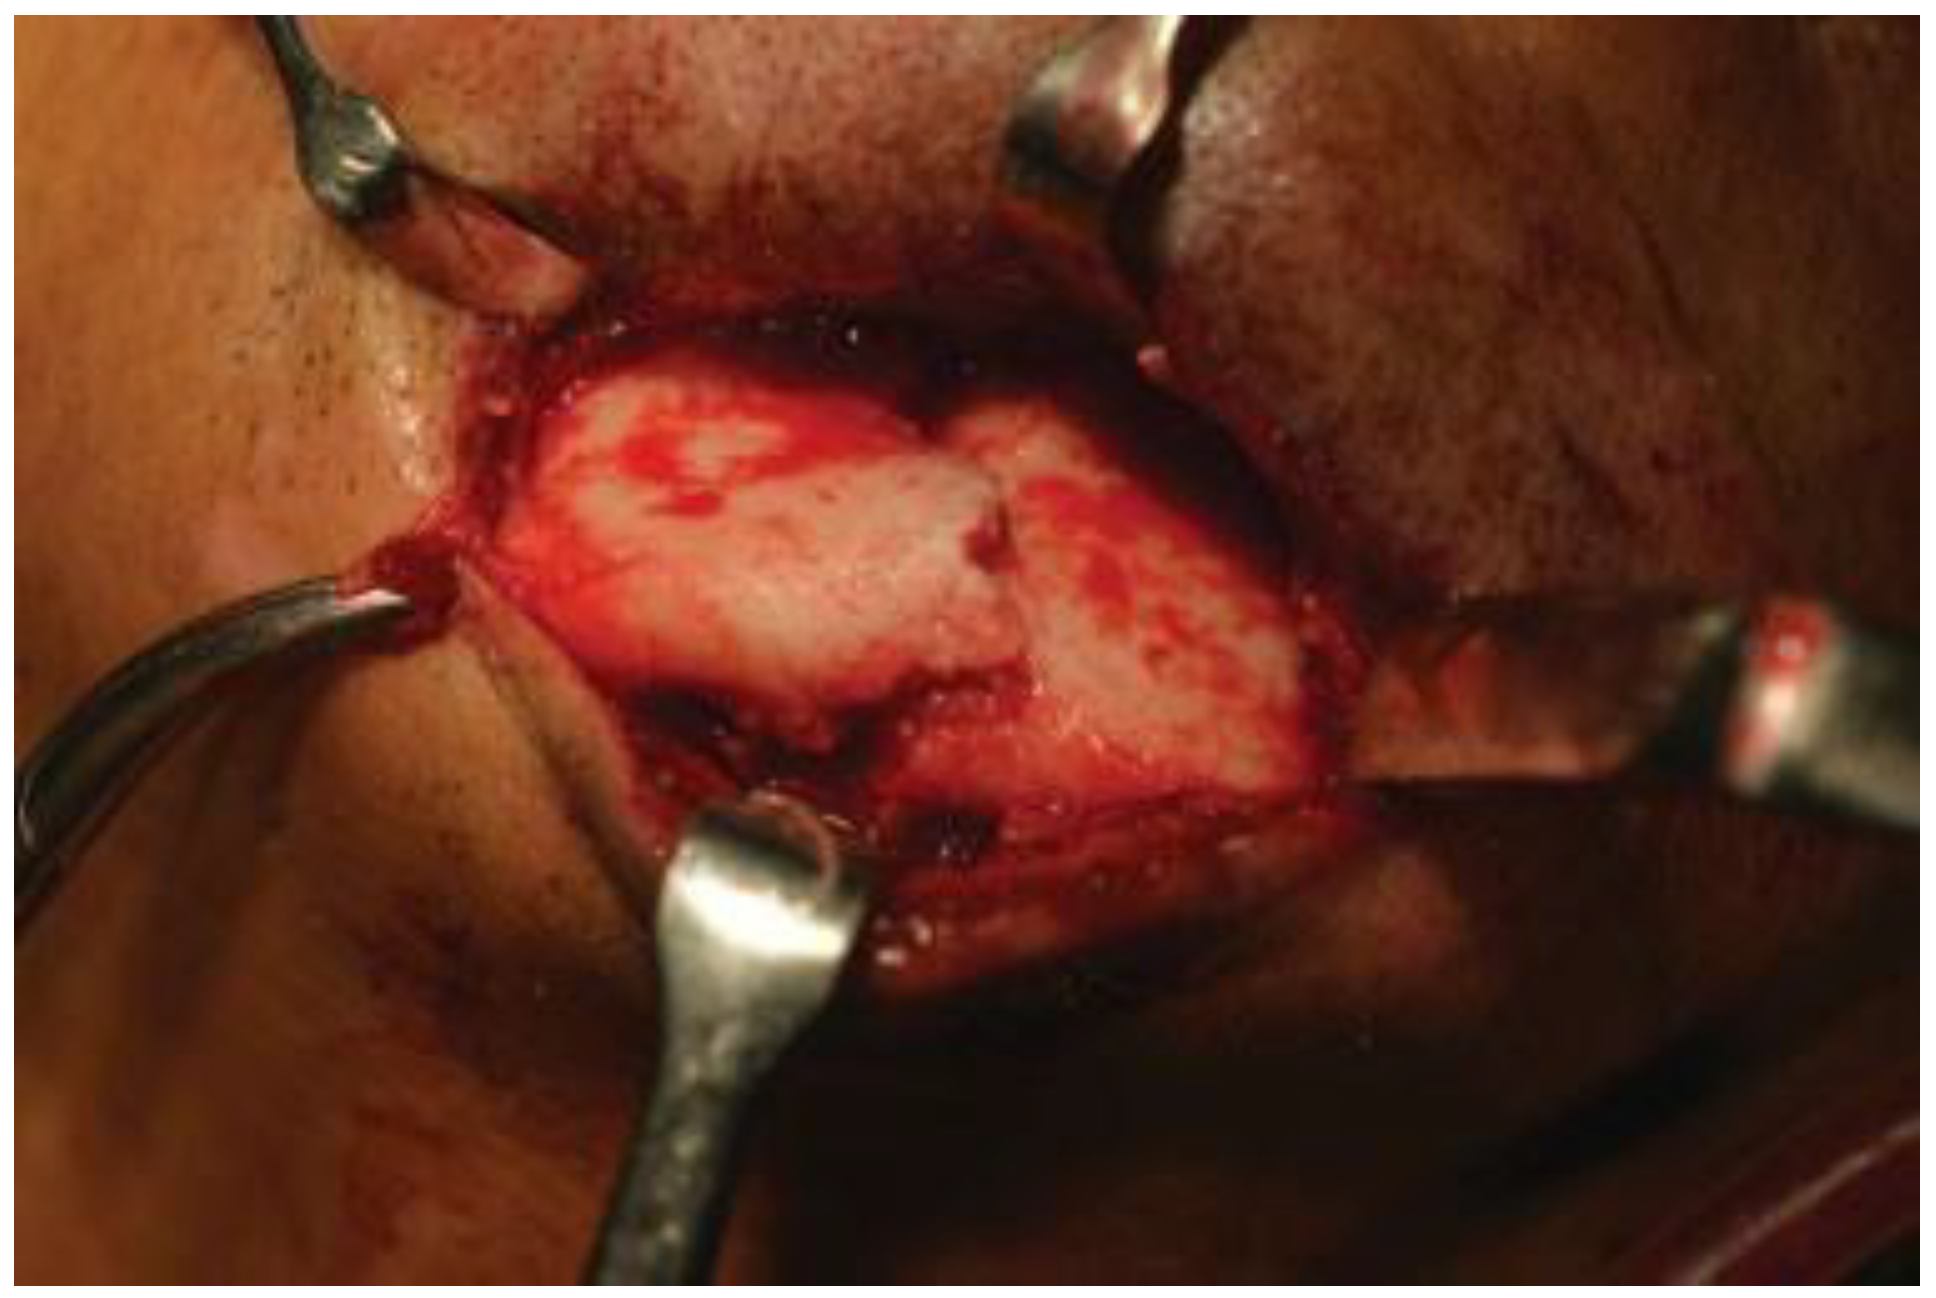

Figure 2. Case 1: Intraoperative photograph of interforaminal mandible fracture exposed extraorally through an existing laceration.

Figure 3. Case 2: Intraoperative photograph of interforaminal mandible fracture exposed extraorally through an existing laceration.

We used a second-generation 3.0 HCS, 24 to 32 mm in length, diameter at the trailing edge of 3.5 mm, smooth shaft with 2.0 mm and at the leading edge 3.0 mm (Synthes Paoli, PA; Figure 1). Patients were operated under local anesthesia or general anesthesia according to the extent of associated injuries and need for their fixation. Part to be operated was prepared with betadine solution and was infiltrated with lignocaine and adrenaline (1:80,000) concentration. An intraoral gingivobuccal/gingivolabial approach or extraoral approach through an existing laceration was taken and careful dissection was done to expose the fracture site (Figure 2 and Figure 3). Fracture segments were reduced along with performing intraoperative intermaxillary fixation to ensure accurate occlusion. The next step is to carefully drill a guiding hole with a 2.5-mm drill bit in the distal fracture fragment. Hand drilling is now commenced with a hollow 2.5-mm drill bit while maintaining the coaxiality in the distal and proximal fragment with the help of a K-wire. The HCS is inserted into the guiding hole along the K-wire with the help of a cannulated T8 StarDrive screwdriver. The screwdriver is engaged and the screw is inserted into the bone using the compression sleeve construct. Both ends of the screw are accommodated in the buccal cortical plate which is necessary to gain interfragmentary compression. When the tip of the compression sleeve contacts the bone, the fracture gap is closed and compressed, and the countersink is performed by holding the compression sleeve stationary and advancing the screw into the bone (Figure 4 and Figure 5). Clinical stability of fixation of fracture was checked intraoperatively by performing labiolingual and superior–inferior movements between the two fracture fragments.